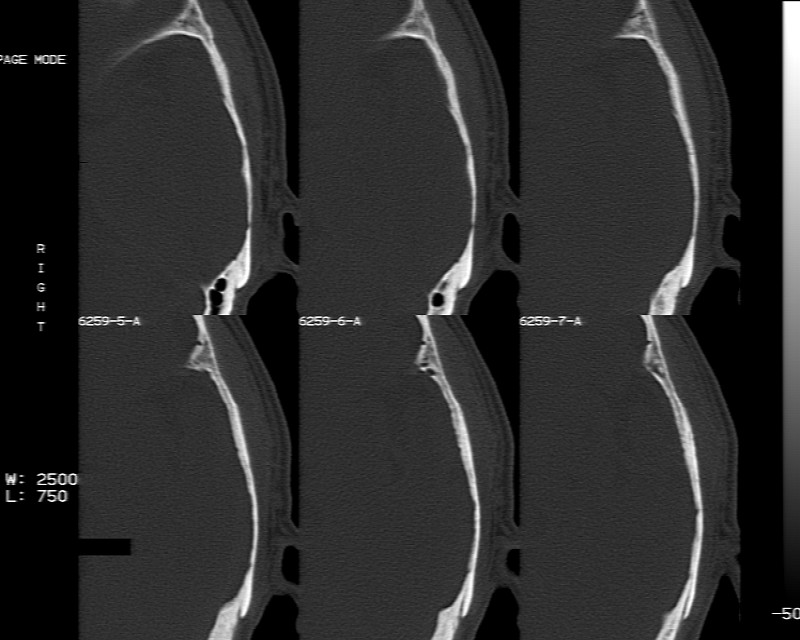

m70y, 2个月前发现左颞部有'包'隆起,近来自觉增大,无外伤无任何不适症状而就医,触诊包块质地较硬无移动无波动无皮温升高,胸片示右上肺陈旧结核....,ct扫描见左颞骨翼板局部内外骨板骨质破坏,似筛孔状,外板侧有骨膜线状增生,伴局部软组织丘状肿块,内板下梭形肿胀硬膜增厚翘起......颅内脑无异常.考虑骨良性病变 1.低度骨感染.   2.嗜酸性肉芽肿. 3.不排外骨结核...建议其穿刺活检,但患者失踪,追踪到结果定将公告.请大家分析.

左颞骨内板不光滑,密度减低,内板下可见新月形的软织密度影。脑实质轻度受压,外板外见膨胀形稍高密度影。考虑嗜酸性肉芽肿。建议增强扫描